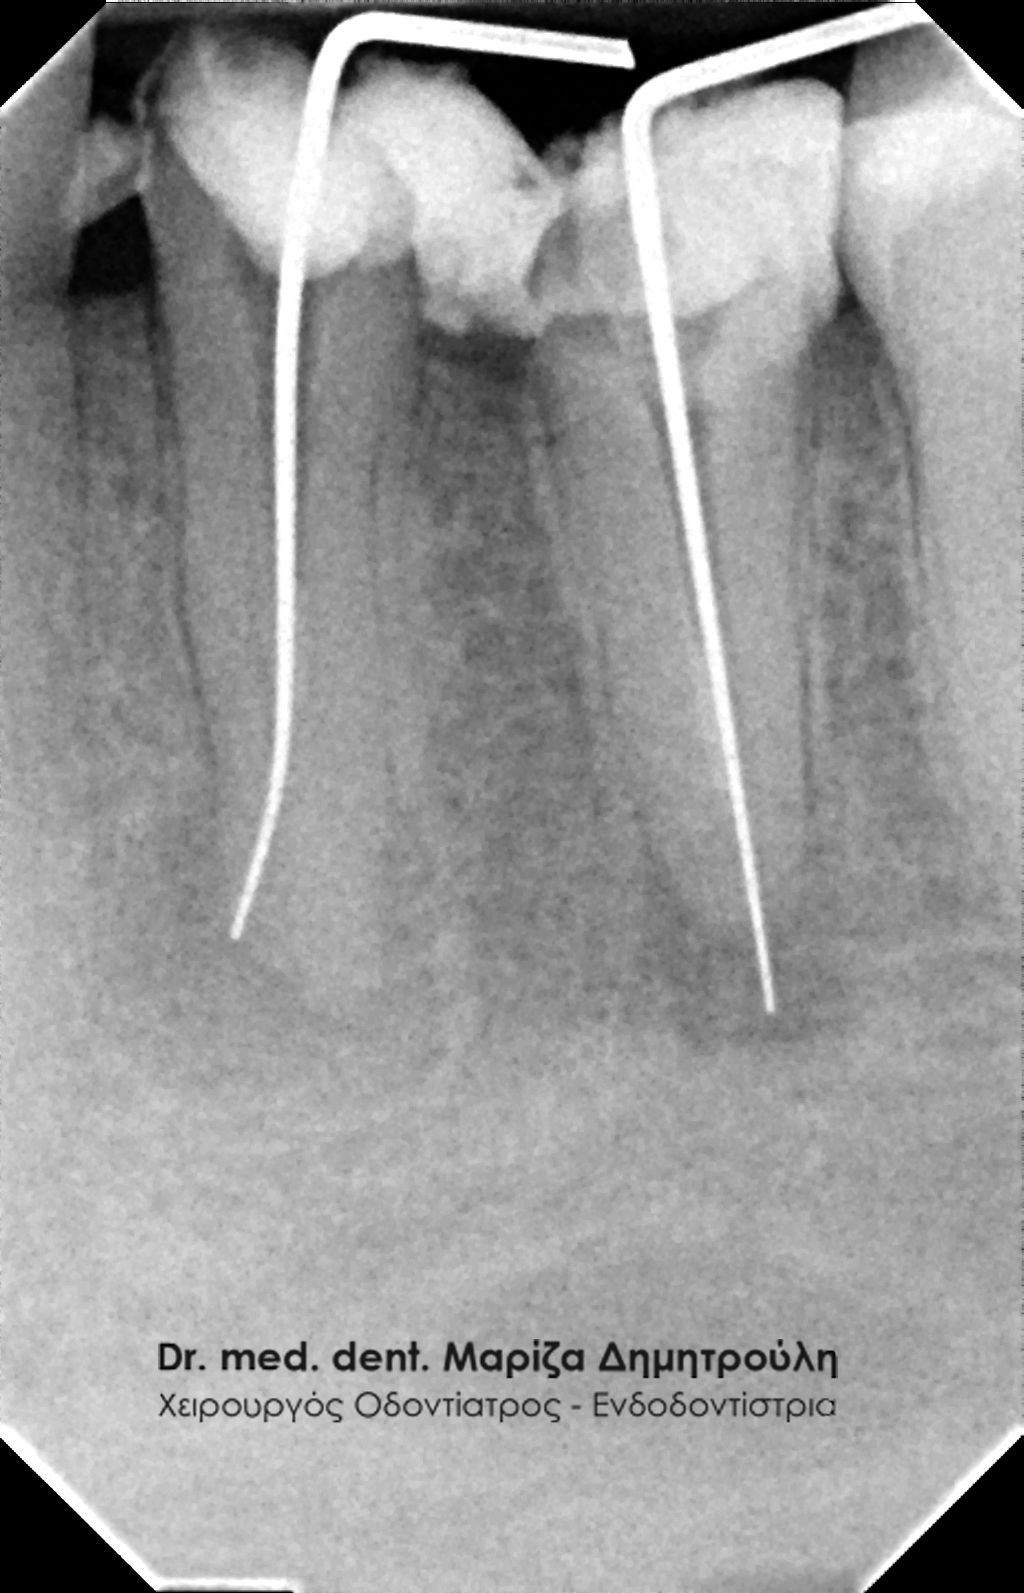

Root canal retreatment

BEFORE

Control of removing the old root canal filling

AFTER